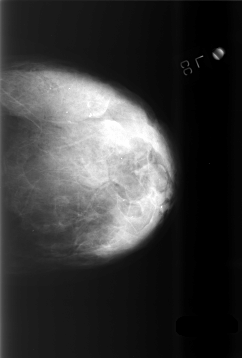

C_0505_1.RIGHT_CC

LEFT_CC LINES 5728 PIXELS_PER_LINE 3872 BITS_PER_PIXEL 12 RESOLUTION 50 NON_OVERLAY